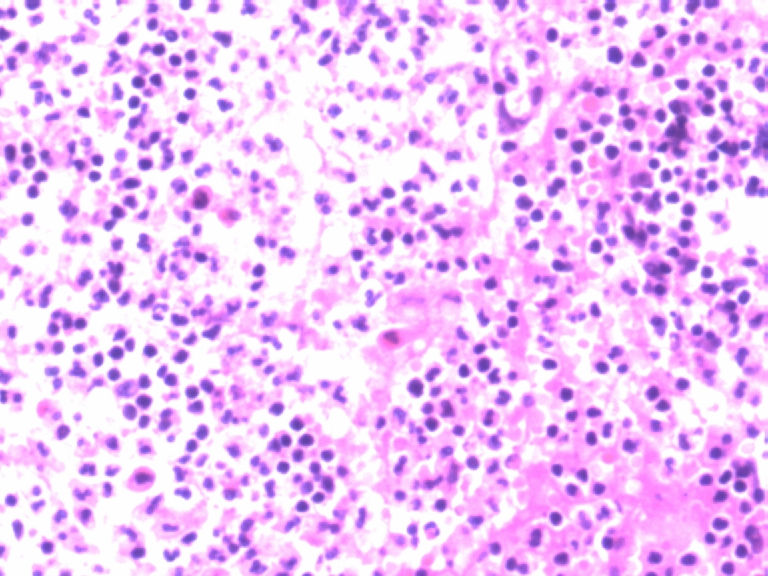

男,50岁,阑尾长7厘米,直径0.4---0.6厘米。剖开:尖端看见淡黄色区,不规则,界限欠清,0.15*0.2厘米,质中。

• 您看了吗?阑尾类癌?图2

图2

考虑阑尾类癌

像类癌,有些粘液,标记一下Syn、CgA,有可能是杯状细胞类癌

按照胃肠胰腺神经内分泌肿瘤WHO2010分类,该例应属于NET G1(神经内分泌瘤,1级)。需标记Syn, CgA, Ki67.

倾向神经内分泌肿瘤,建议做CgA、SYN、Ki-67检查。

阑尾的神经内分泌肿瘤我们已经碰到好几例了,一般都在阑尾尖端,取材一定要规范,这样可以减少漏诊率。